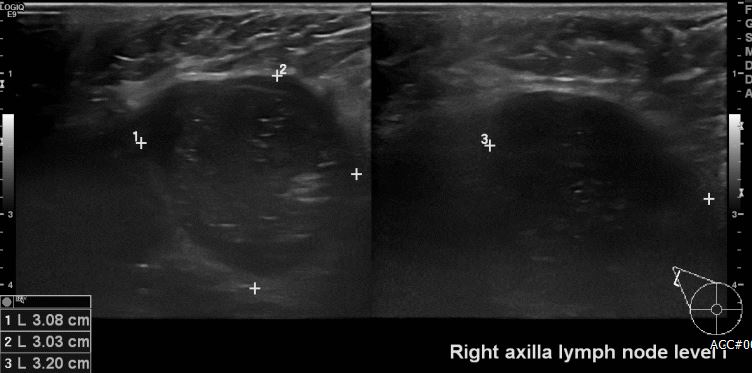

상기 환자 건강검진상 이상 소견으로 내원하신 50대 여성 분으로 우측 유방 전체 비대 및

우측 겨드랑이 림프절 비대 있어 조직검사 시행하여 우측 겨드랑이 전이암 진단 되었습니다.